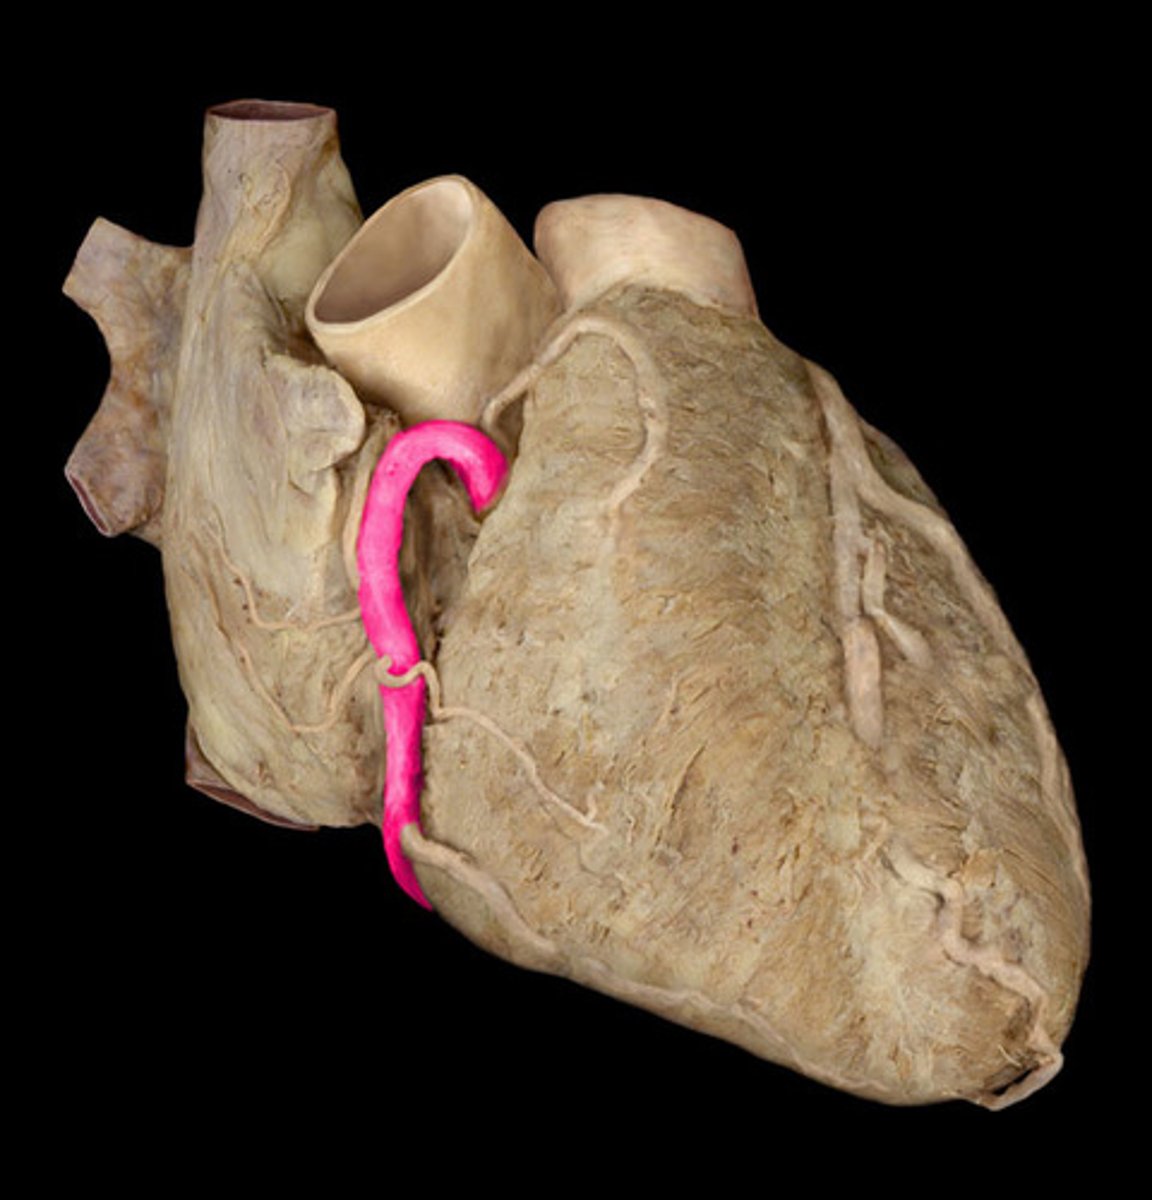

left coronary artery

anterior interventricular artery or left anterior descending artery (of left coronary artery)

circumflex artery (of left coronary artery)